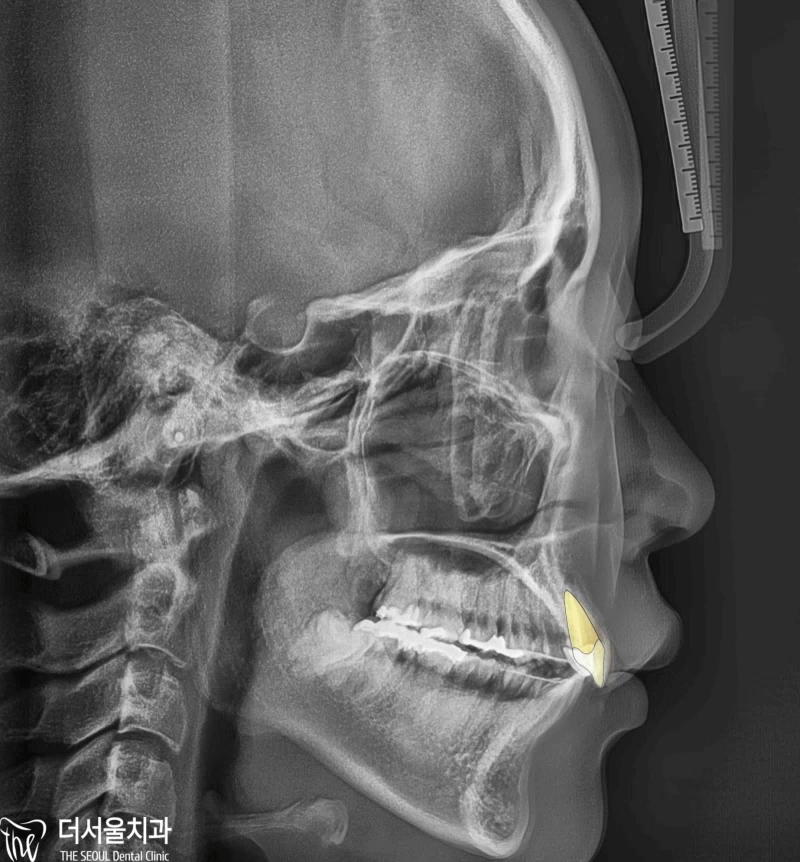

부정교합 2급 이라는 것은, 하악보다 상악이 더 전방에 위치되거나 또는 상악의 치아들이, 하악 치아들보다 더 앞쪽에 위치되어 있는것을 뜻하며

증세를 갖고 계셨던 분의 임상 증례를 보여드립니다. 교정 치료를 통해서 2급 부정교합이 개선 되었으며 치료를 끝으로, 턱 끝에 보형물